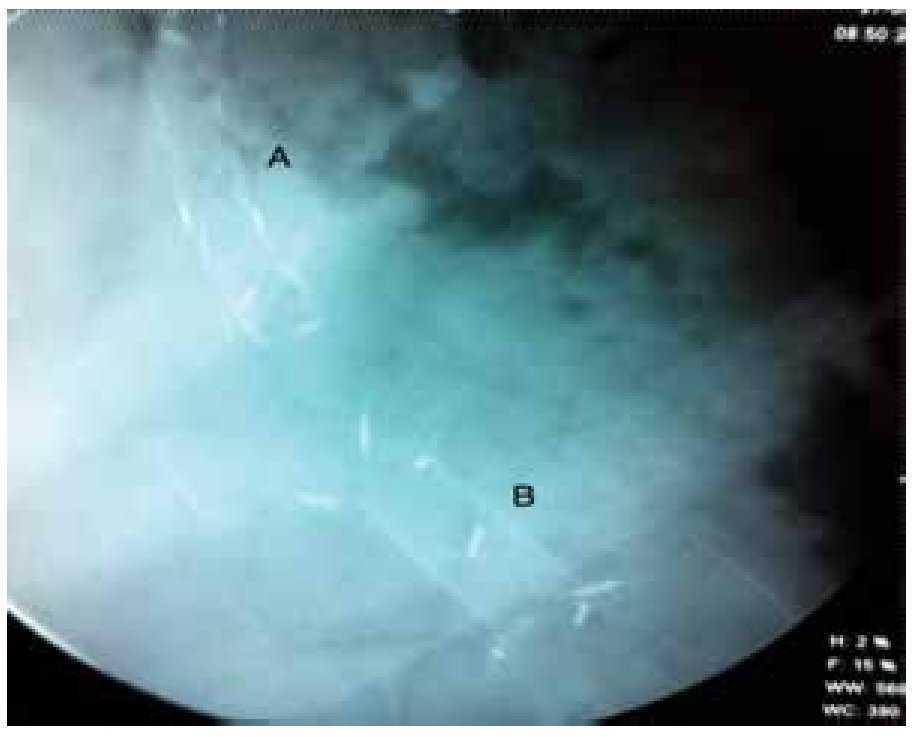

Figura 1. Pasos del procedimiento del DE guiado por USE de una CIA. A) Imagen tomográfica de una CIA sintomática. B) Imagen endosonográfica de la CIA. C) Punción bajo guía ultrasonográfica de la CIA. D) Imagen fluoroscópica de una CIA con medio de contraste y una guía 0.035" en su interior. E) Imagen endoscópica de la guía que conduce a la CIA. F) Dilatación con balón del trayecto de la fístula entre el tracto gastrointestinal y la CIA. G) Imagen endoscópica de una prótesis plástica doble cola de cochino en el interior de la CIA. H) Imagen endoscópica de un catéter naso-quístico que conduce a la CIA. I) Imagen fluoroscópica de la prótesis plástica doble cola de cochino y el catéter naso-quístico en el interior de la CIA.

Figura 2. Utilización de PMAETR en el DE guiado por USE de CIA.